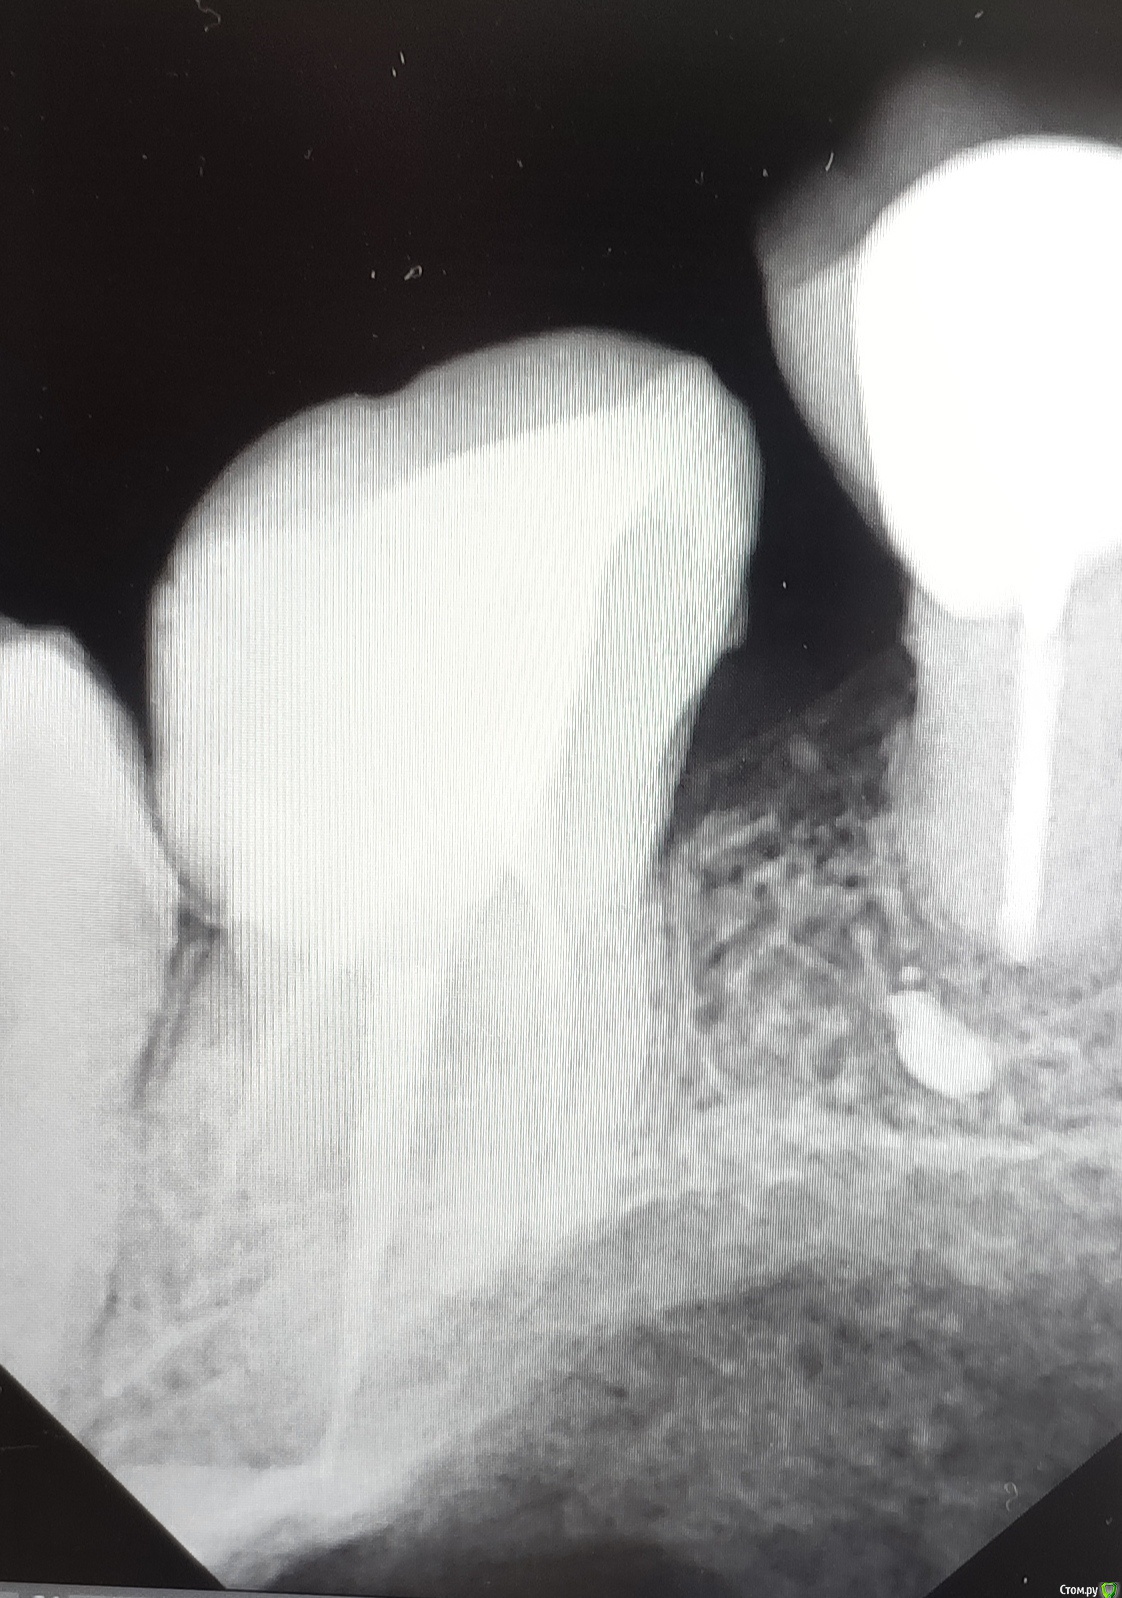

Александр9 Опубликовано 24 августа, 2020 Поделиться Опубликовано 24 августа, 2020 Три недели назад поставили постоянную пломбу после лечения пульпита. Небольшая чувствительность зуба осталась. Поэтому сегодня сделал рентгеновский снимок на котором новый врач установил, что один канал недолечен, и возможно есть еще и четвертый канал. Изначально мне не понравилось, что при лечении была плохо сделана анестезия, поэтому перелечиваться хочу у другого доктора. Нужен совет, исходя из практики, могу ли я требовать полного возврата суммы за лечение? В клинике предлагают перелечивание другим доктором за дополнительные деньги, и что в любом случае два канала были вылечены и полный возврат невозможен. P.S. Я еще сделал КТ, но не разобрался с просмотрщиком и выложить кадры оттуда не могу. Ссылка на комментарий

Александр9 Опубликовано 24 августа, 2020 Автор Поделиться Опубликовано 24 августа, 2020 Мне еще сказали, что возможно есть четвертый канал. Подскажите пожалуйста, это видно на прилагаемом снимке? А если нет, то на КТ он будет виден (если есть)? Ссылка на комментарий

Doc Опубликовано 26 августа, 2020 Поделиться Опубликовано 26 августа, 2020 На таком снимке вообще сложно что-то увидеть, но у этих зубов четвертый канал совсем не редкость. На КТ должно быть видно лучше. Ссылка на комментарий